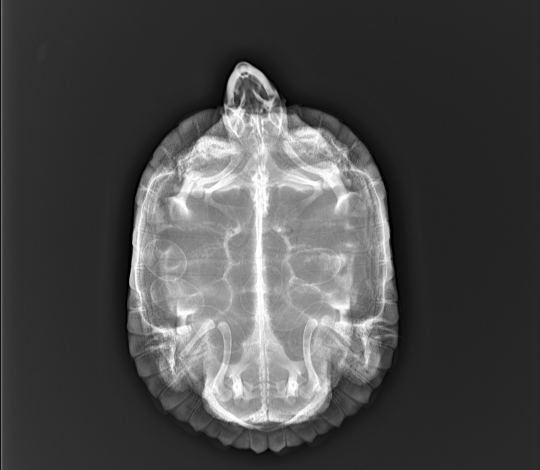

9.  06.06 сделали рентген - у черепахи 7 яиц

06.06 сделали рентген - у черепахи 7 яиц

Если есть возможность, приложите, пожалуйста, рентген.